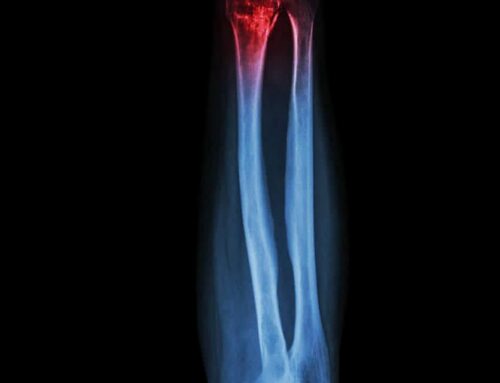

Diagnostic Imaging: X-rays

• X-rays are the primary tool for diagnosing fractures and are usually available on-site.

• The injured area will be positioned for several images taken from different angles.

• Results will confirm the type, location, and severity of the fracture — or rule out a break entirely.